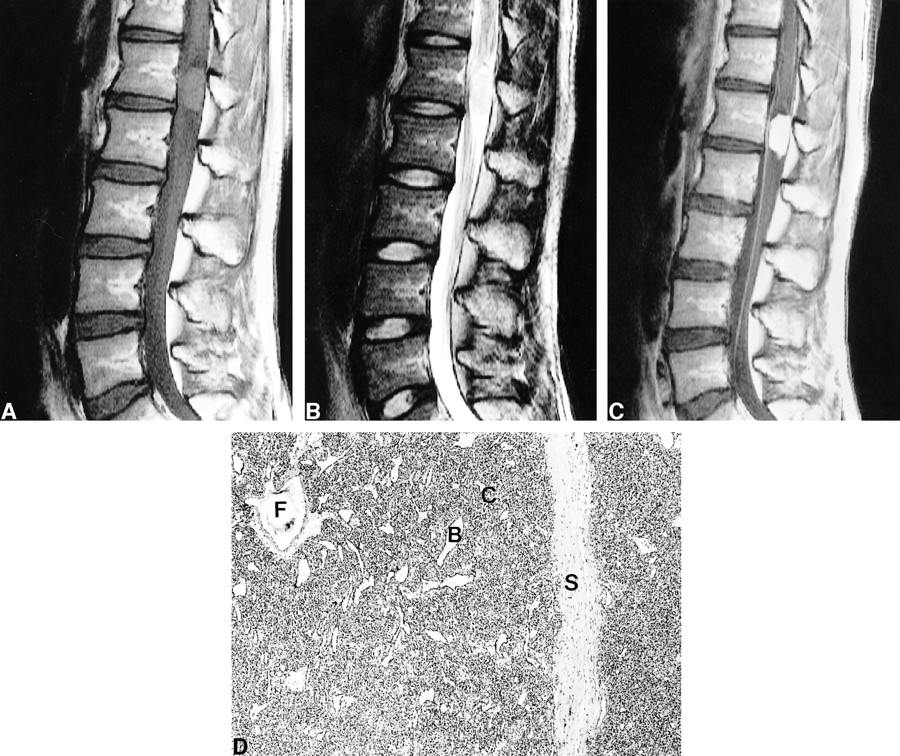

Case 3 (Figure 3)

Case 3.

Unenhanced sagittal (A) and contrast-enhanced sagittal (B) and axial (C) T1-weighted MR images show a markedly enhancing intradural extramedullary mass displacing the spinal cord anteriorly at the T4–T5 level.

A 51-year-old man was hospitalized in our institution for evaluation and treatment of claudication and radiating pain to both lower extremities. These symptoms were aggravated 1 day prior to admission. Physical examination confirmed decreased motor strength of both lower extremities in association with hypesthesia and paresthesia at the area below the T5 level.

MR imaging of the thoracic spine revealed a well-demarcated, intradural extramedullary mass at T4–T5 level. The mass was attached to and broadly based on the posterior dura matter, compressing the cord and displacing it anteriorly.

The preoperative diagnosis was meningioma.

At surgery, a 2.0 × 1.0 × 1.0-cm3 bright reddish mass with a smooth surface was observed within the dural sac, and was attached to the dura. Gross total removal of the mass was performed. Histologically, the mass was composed of capillary-sized small vessels of lobular configuration. Each vessel was lined by flattened mature endothelial cells. The histologic features were similar to Case 1; however, the density of vascular channels was less, and intervening connective tissue was more abundant.